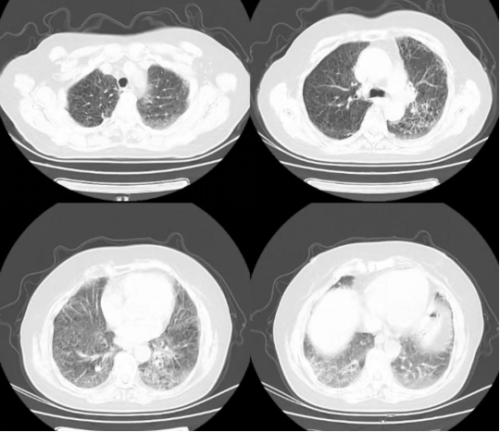

CT 影像:11 月 27 日复查胸部 CT,可见双肺磨玻璃渗出影明显吸收,对比 11 月 18 日影像,肺部病变改善显著。

11月27日肺CT:

11月18日肺部 CT

11月27日肺部CT